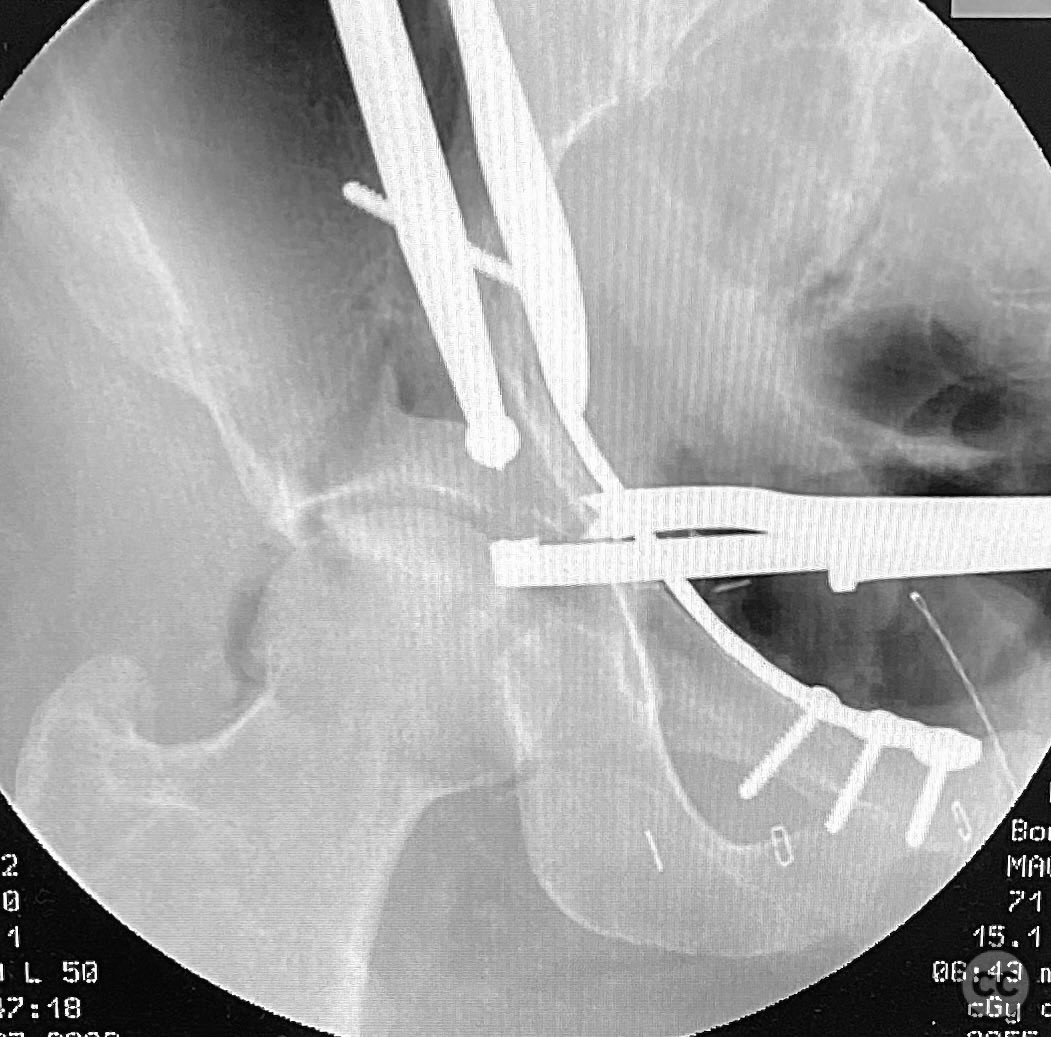

Anatomical surgical approach:  A classical ilioinguinal approach was performed, developing the lateral, middle, and medial windows. The intrapelvic interval was used to access the quadrilateral surface and posterior column. The rhomboid cortical fragment was excised to allow direct visualization and manipulation of the impacted posterior medial dome fragment. Reduction was achieved using a spiked pusher under fluoroscopic guidance. The defect was filled with morselized allograft, and the rhomboid fragment was anatomically reduced. The anterior column was stabilized with a contoured plate. Posterior column reduction was further improved using a reduction clamp applied with one tine lateral to the anterior inferior iliac spine (AIIS) and the other on the quadrilateral surface via the middle window, followed by lag screw fixation.

This case demonstrates that certain impacted dome fragments, which are otherwise inaccessible, can be directly addressed by temporarily removing overlying cortical fragments. The ilioinguinal approach, specifically through the middle window, provided unobstructed access for clamp placement and direct manipulation of both anterior and posterior column fragments. Sequential reduction and stabilization were facilitated by direct visualization and intraoperative fluoroscopy, allowing for anatomical restoration of the articular surface.